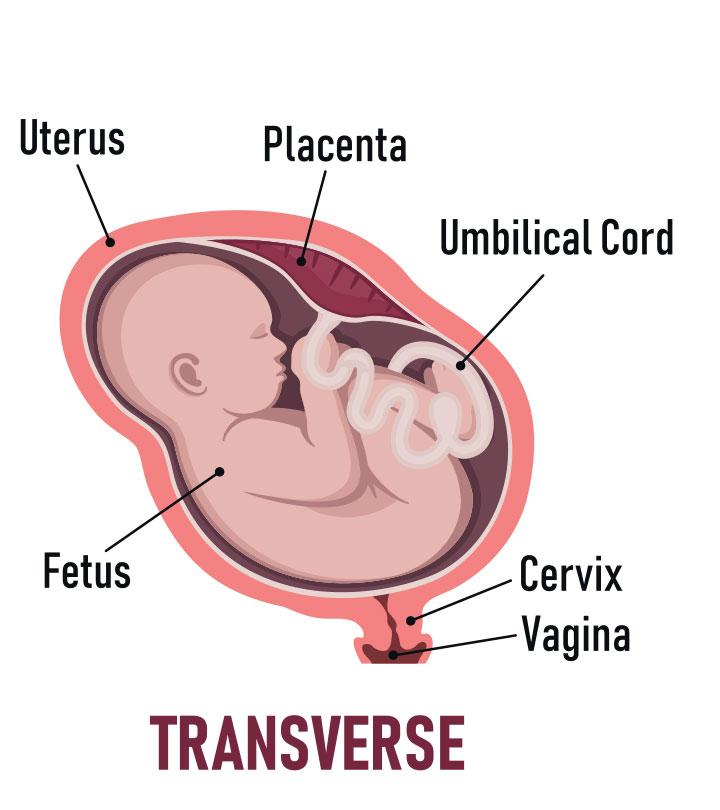

- During acid refluxiBackflow of digestive acid from the stomach through the esophagus, causing a burning sensation in the chest. , as it causes discomfort.